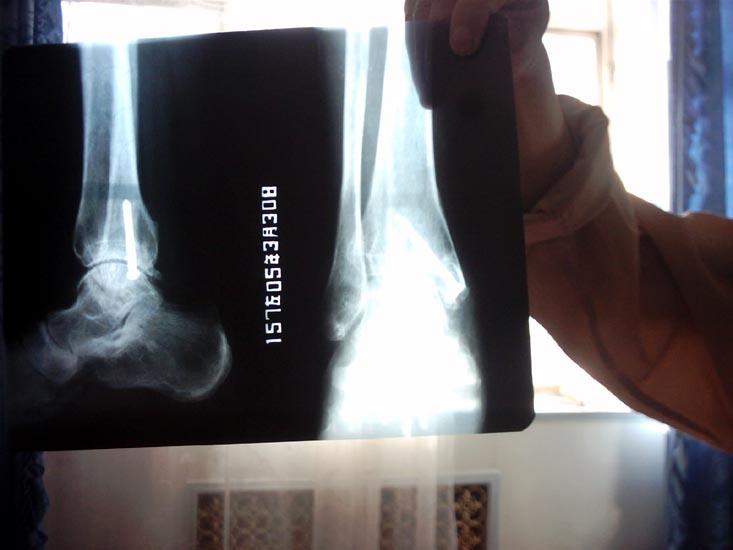

高精度图片高精度图片

骨折的X光照片

手术时,我听见医生们议论:“真是惨无人道,太卑鄙了,给人打成这样。”手术把我的脚关节骨盖摘除,大骨用螺丝钉固定(螺丝钉至今未取)。在我手术期间,他们为了封锁消息,把跟我一同送来一起迫害的同修叫到办公室问:“某某的腿那天晚上有人打了吗?”同修说:“吸毒人员打的。”又问:“值班队长不在吗?”同修说:“队长知道。”他们马上说:“队长不会这样做,以后不许胡说!”8月3日将我送回三大队,可马成林却不见了。有几个吸毒人员偷偷告诉我,队里怕事情败露,以调查为由,把马成林带走了,实际上是放了。后来我的亲戚来平安台向队长询问我腿的情况,队长却说是我自己绊的。我的亲戚说:“我如查出不是绊的,是你们打的,我就告你们。”后来连进财找我单独谈话:“某某,你的腿是马成林打的,是上面的意思,跟我可没关系,你出去千万别找我麻烦,我拖家带口也不容易啊!”此后,怕我告他,经常假意关心我。2004年平安台的法轮功修炼者都被集中到六大队十六中队,他们怕恶行败露,把我一人关到二楼十七中队,不准见太阳,吃饭也不让出去,让互监打进来吃。2004年5月又把我转到十八中队,始终封锁消息。我去要医院给我拍的片子,他们不给,我的家人也到康泰医院去要我的手术记录、片子,可医院告诉我家人,劳教所把片子、治疗记录全部取走了。2005年3月7日从劳教所解教回家后,我得知原工作单位解除了我的劳动合同。我到医院又拍了左踝关节正侧位片,片上螺丝钉清晰可见,确诊左踝仍有慢性创伤性关节炎。